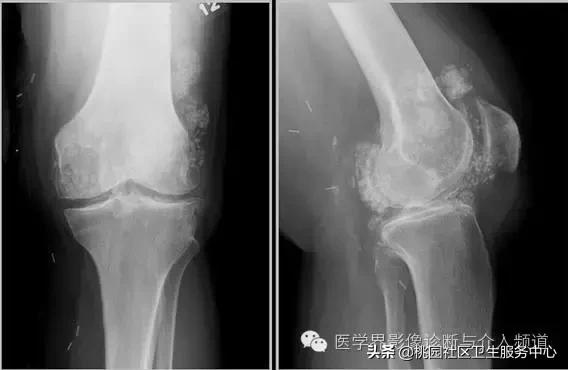

3、CPPD(焦磷酸钙沉积症)相关性钙化

CPPD(焦磷酸钙沉积症)

4、痛风石

为尿酸盐沉积形成,发生在关节周围软组织、包括韧带、肌腱、滑囊,眼、耳、鼻、喉、皮肤, 50%的钙化为X线平片可见。

痛风石,可见软组织肿胀及钙化灶。